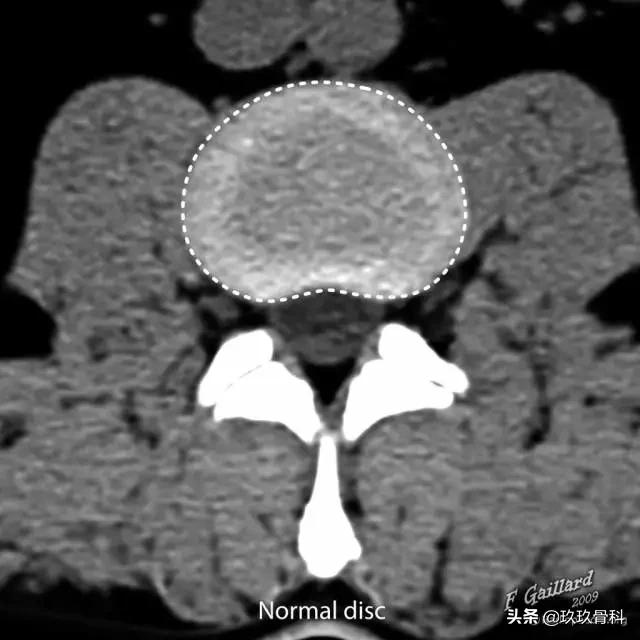

图 1 正常椎间盘示意图,椎间盘由周围的纤维环和中心的髓核组成

图 2 正常椎间盘在相邻两个椎体之间,周围不超出椎体的边缘